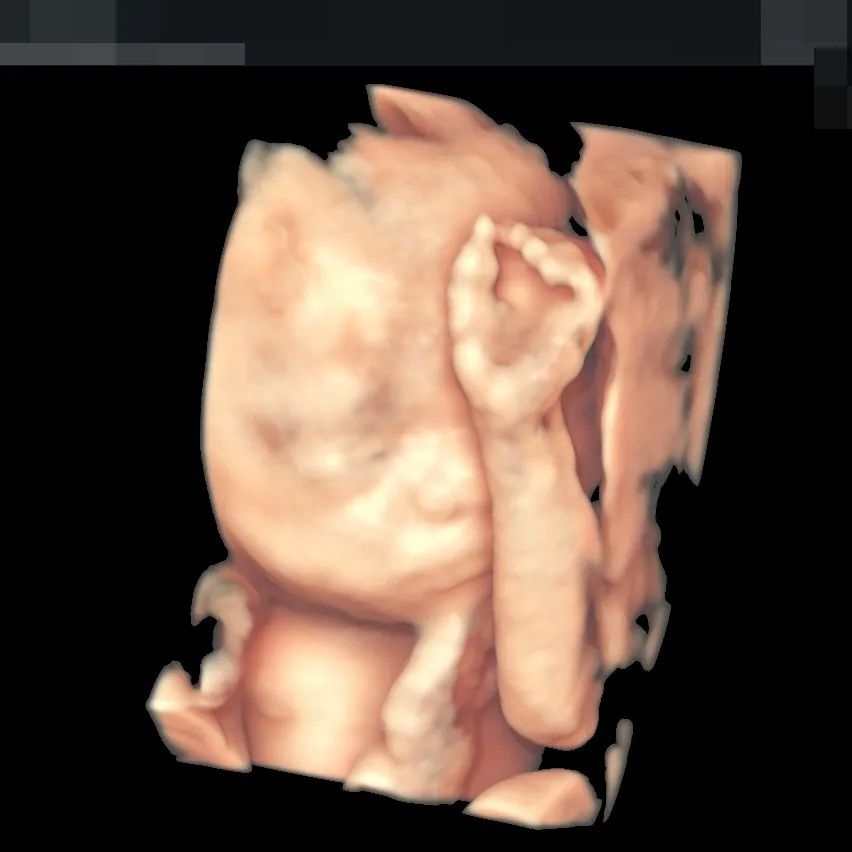

▲赵女士已经超过最佳检查时间2周,和平超声科医生在保证安全的状况下,为她重新测算数值,最终顺利完成筛查